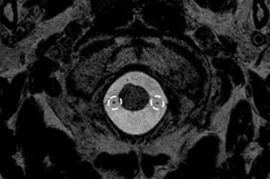

Axial CT of superior orbital fissure (arrows) and optic canal (asterisks).

Axial CT of foramen rotundum (asterisks).

Axial CT of foramen ovale (arrows).

Axial CT of facial canal (arrows).

Axial CT of internal auditory meatus (arrows).

Axial CT of jugular foramen (asterisks).

Axial CT of hypoglossal canal (asterisks).